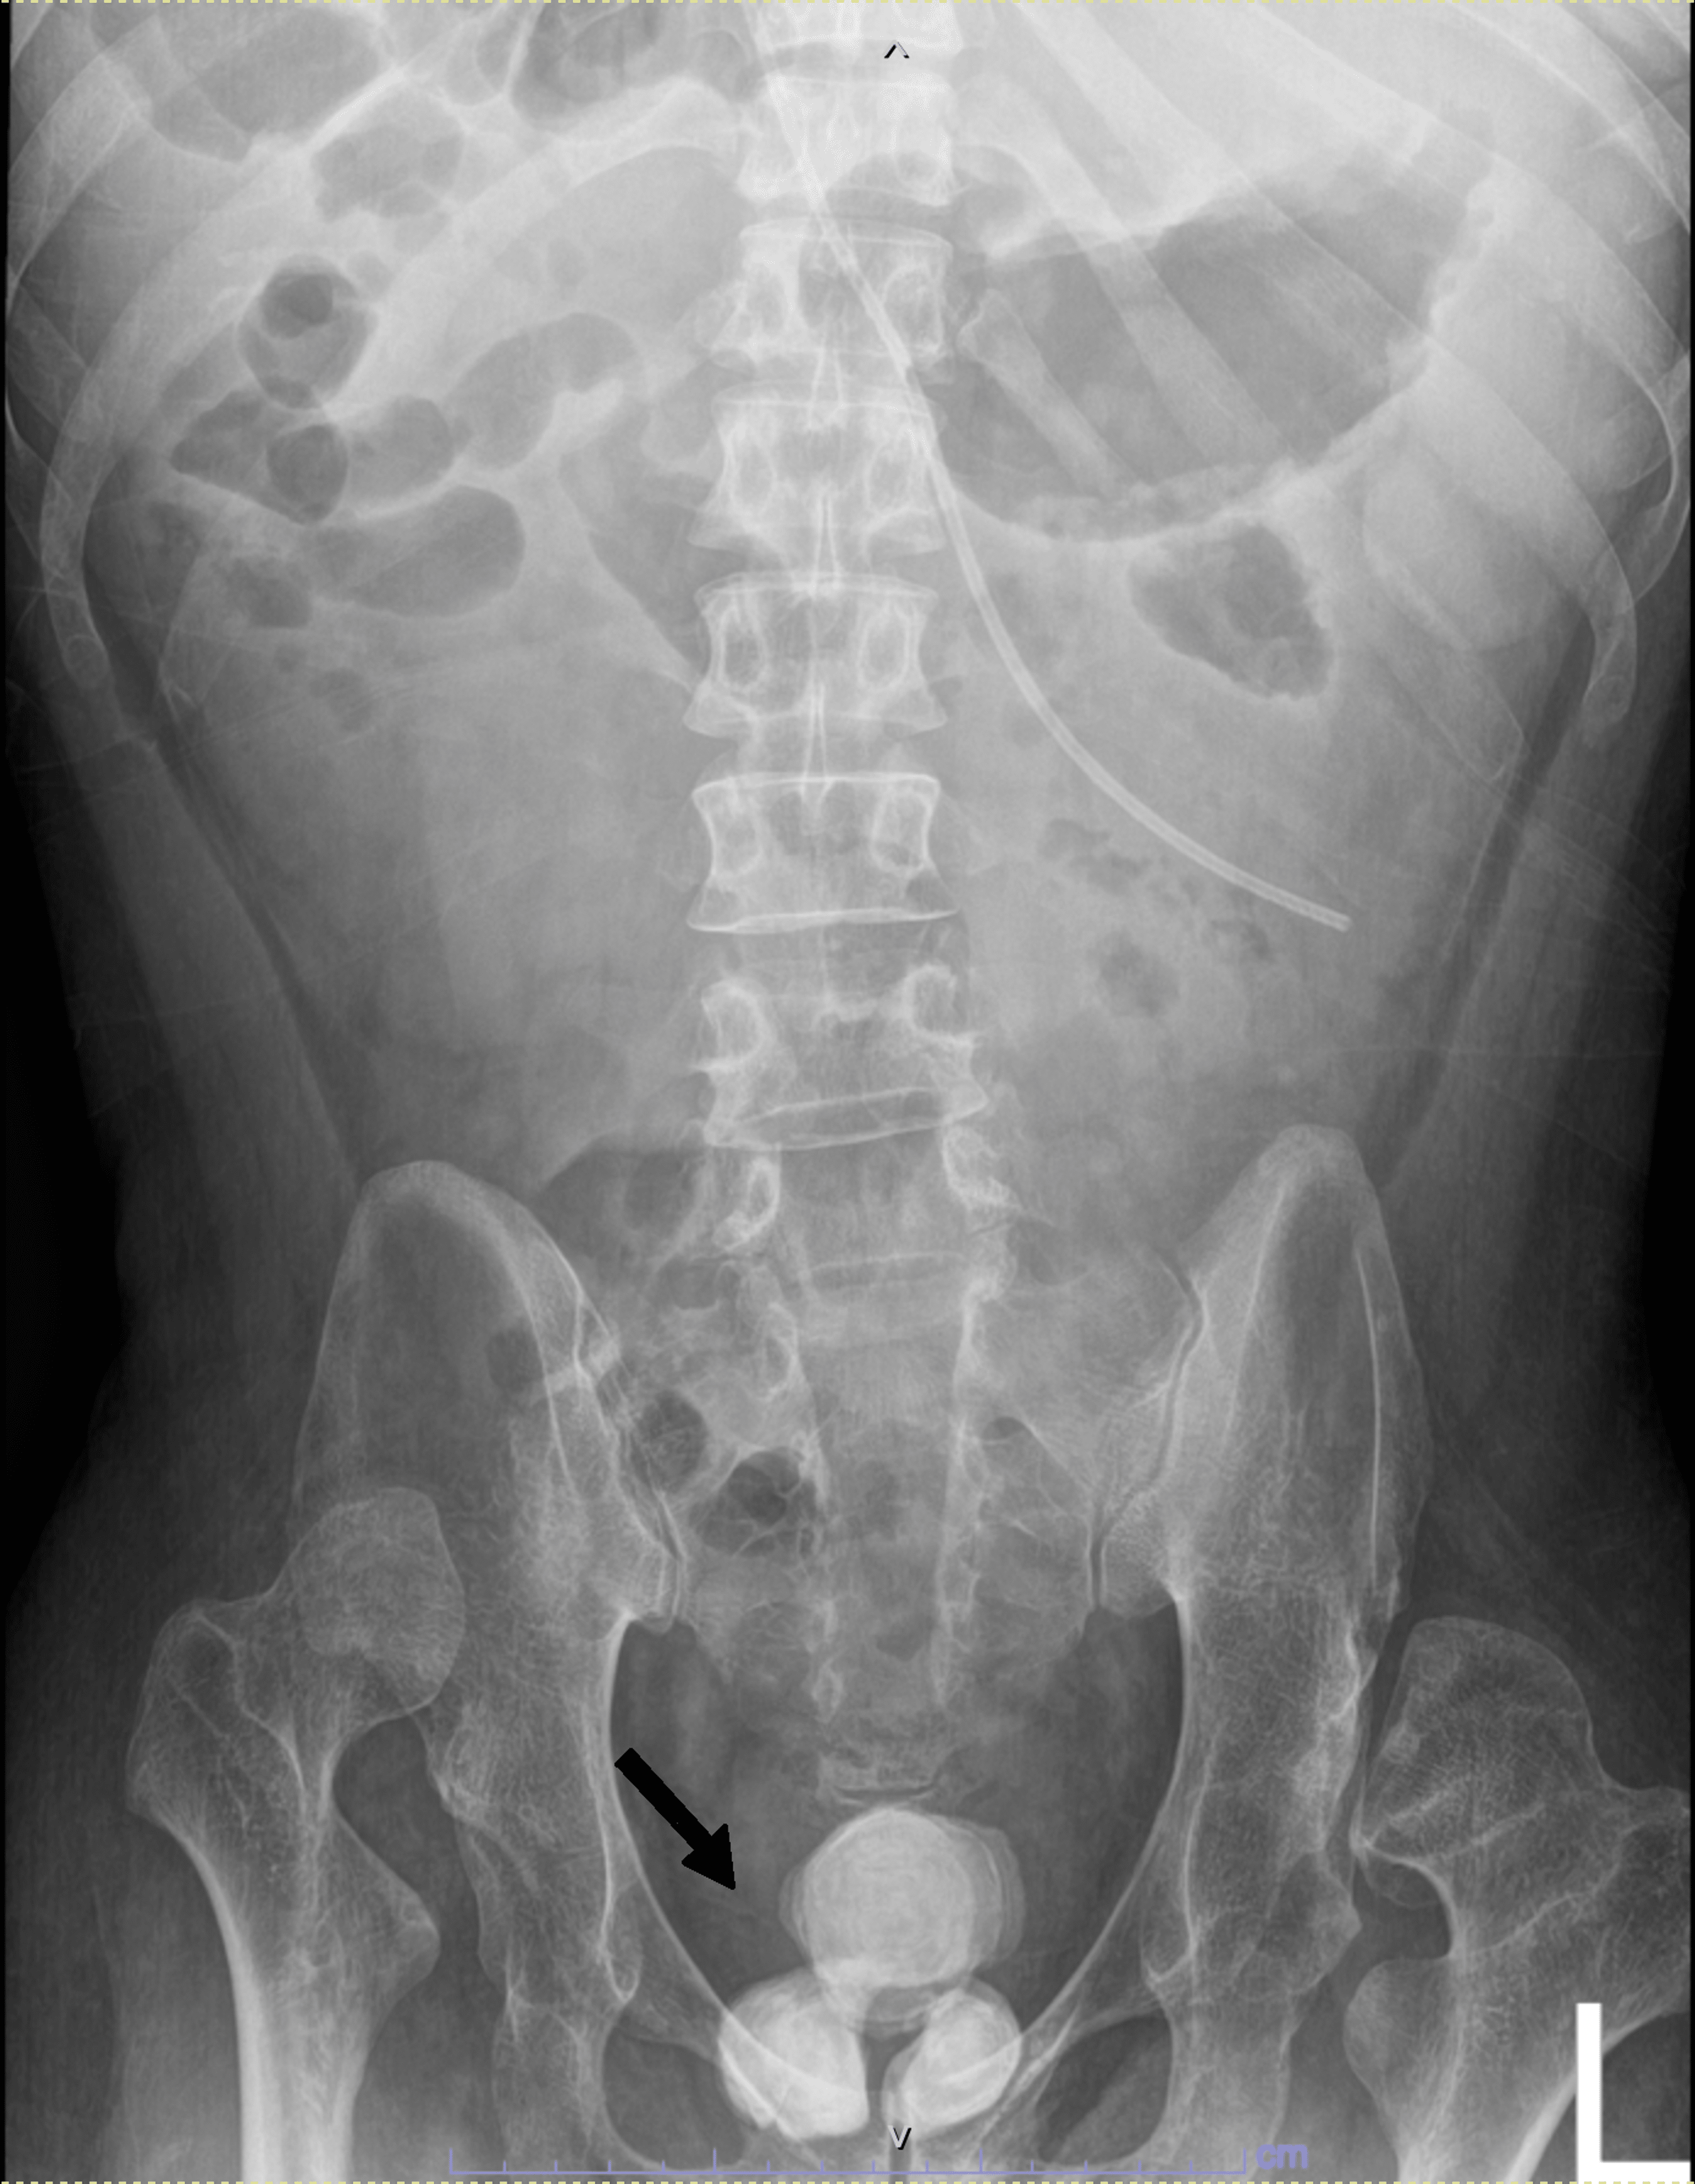

Supine KUB (A) showing numerous radiopaque stones at the projection of

Supine KUB (A) showing numerous radiopaque stones at the projection of Radiopaque Bladder Stones The mean age at occurrence is ~6. This article reviews types of urinary calculi and their imaging appearances, presents direct and secondary imaging findings of urolithiasis, and provides an. In general, us is poor at localizing ureteral stones, especially in the absence of. If kidney, ureter, and bladder radiographs fail to depict the stone, ct may be needed to follow. Radiopaque Bladder Stones.